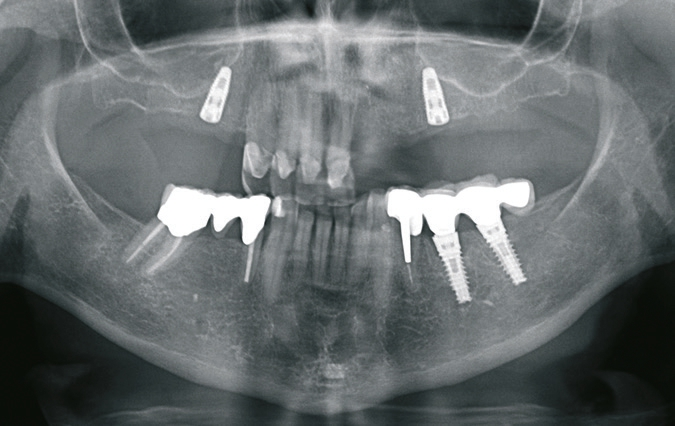

Nach Abschluss der Vorbehandlung erfolgte die Implantatplanung. Dazu wurde die neu angefertigte ideal ausgerichtete Drahtklammerprothese dubliert und das Duplikat als Röntgenschablone verwendet. Mithilfe der Planungssoftware NobelClinician ® (Nobel Biocare, Göteborg, Schweden) wurden möglichst weit distal und damit unmittelbar vor dem Sinus maxillaris zwei Implantate in regio 15 und 25 geplant (Abb. 6). Anschließend wurde die Röntgenschablone im Bereich der geplanten Implantatpositionen angepasst, sodass sie als Orientierungshilfe bei der Implantation verwendet werden konnte (Abb. 7). Die Implantationen erfolgten unter Lokalanästhesie in einer Sitzung. Es wurde ein geschlossenes Einheilverfahren gewählt. Zur postoperativen Kontrolle der Implantatpositionen wurde eine Orthopantomografie angefertigt (Abb. 8).

Sechs Monate nach Fertigstellung der Oberkieferhybridprothese folgte die definitive Versorgung im Unterkiefer. Die verblockten und nicht passgenauen Kronen 34-35i-36i wurden entfernt und ein direktes Provisorium für den Zahn 34 angefertigt. Die beiden Implantate 35i und 36i wurden mit standardisierten Healing-Abutments provisorisch versorgt. Nach chirurgischer Weichteilkorrektur und Nachpräparation des Pfeilerzahnes 34 wurde die Situation abgeformt und mit neuen einzelnen VMK-Kronen und -Implantatkronen versorgt (Abb. 20 u. 21).